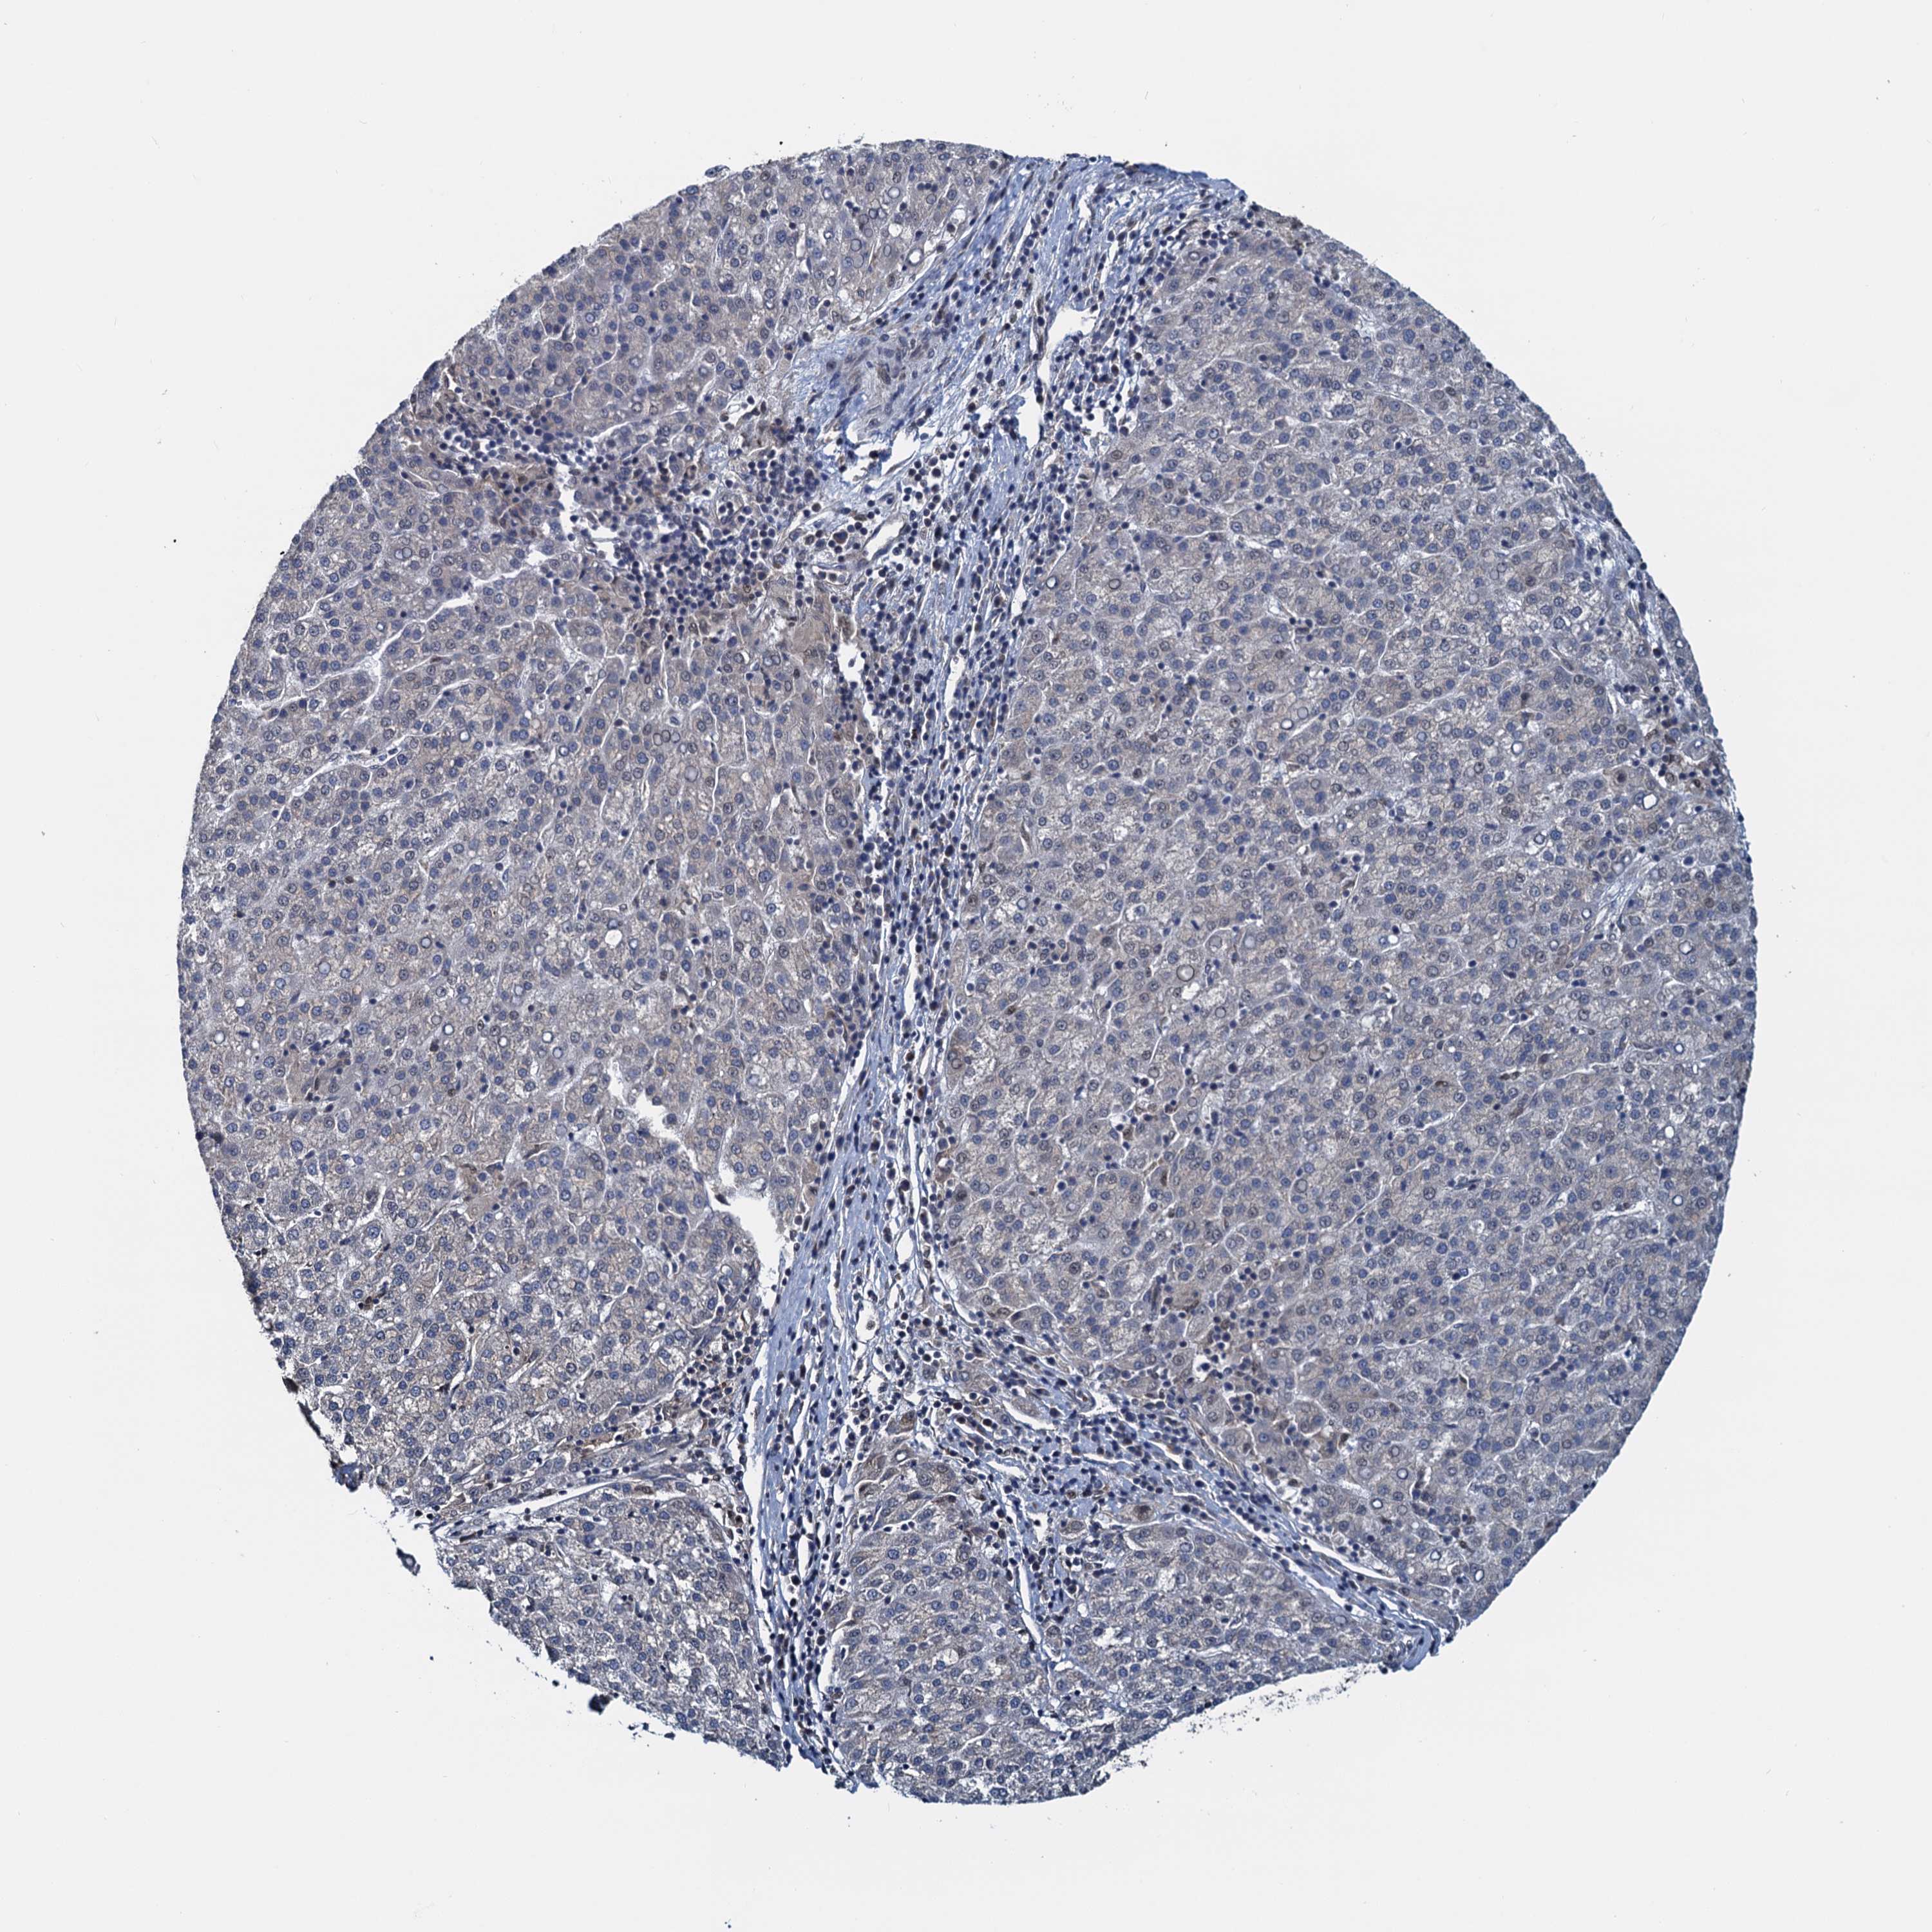

LIVER CANCER - Protein expressioni

A mouse-over function shows sample information and annotation data. Click on an image to view it in a full screen mode. Samples can be filtered based on level of antibody staining by selecting one or several of the following categories: high, medium, low and not detected. The assay and annotation is described here.

Note that samples used for immunohistochemistry by the Human Protein Atlas do not correspond to samples in the TCGA dataset.

Antibody stainingi

Antibody staining in the annotated cell types in the current human tissue is reported as not detected, low, medium, or high, based on conventional immunohistochemistry profiling in selected tissues. This score is based on the combination of the staining intensity and fraction of stained cells.

Each image is clickable and will lead to virtual microscopy that enables deeper exploration of all samples and also displays staining intensity scores, fraction scores and subcellular localization as well as patient and tissue information for each sample.

Antibody HPA041514

Staining

High

Medium

Low

Not detected

Intensity

Strong

Moderate

Weak

Negative

Quantity

>75%

75%-25%

<25%

None

Location

Nuclear

Cytoplasmic/membranous

Cytoplasmic/membranous,nuclear

Cholangiocarcinoma

Carcinoma, Hepatocellular, NOS